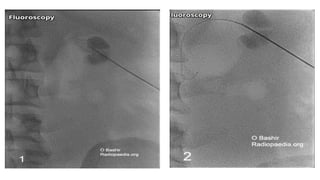

Equipment • USG orfluoroscopy guidance • LA 1% or 2% lignocaine • 18 gauge puncture needle • 0.035 inch stiff guidewire • Water soluble contrast media • Dilators • Pigtail drain (8 French)

• 8.